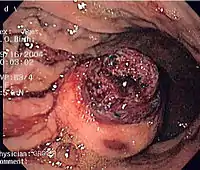

Imaging

The purpose of radiologic imaging is to locate the lesion, evaluate for signs of invasion and detect metastasis. Features of GIST vary depending on tumor size and organ of origin. The diameter can range from a few millimeters to more than 30 cm. Larger tumors usually cause symptoms in contrast to those found incidentally which tend to be smaller and have better prognosis.[5][14] Large tumors tend to exhibit malignant behavior but small GISTs may also demonstrate clinically aggressive behavior.[15]

Barium fluoroscopic examinations and CT are commonly used to evaluate the patient with abdominal complaints. Barium swallow images show abnormalities in 80% of GIST cases.[15] However, some GISTs may be located entirely outside the lumen of the bowel and will not be appreciated with a barium swallow. Even in cases when the barium swallow is abnormal, an MRI or CT scan must follow since it is impossible to evaluate abdominal cavities and other abdominal organs with a barium swallow alone. In a CT scan, abnormalities may be seen in 87% of patients and it should be made with both oral and intravenous contrast.[15] Among imaging studies, MRI has the best tissue contrast, which aids in the identification of masses within the GI tract (intramural masses). Intravenous contrast material is needed to evaluate lesion vascularity.

Preferred imaging modalities in the evaluation of GISTs are CT and MRI,[17]: 20–21 and, in selected situations, endoscopic ultrasound. CT advantages include its ability to demonstrate evidence of nearby organ invasion, ascites, and metastases. The ability of an MRI to produce images in multiple planes is helpful in determining the bowel as the organ of origin (which is difficult when the tumor is very large), facilitating diagnosis.

Small GISTs

Since GISTs arise from the bowel layer called muscularis propria (which is deeper to the mucosa and submucosa from a luminal perspective), small GIST imaging usually suggest a submucosal process or a mass within the bowel wall. In barium swallow studies, these GISTs most commonly present with smooth borders forming right or obtuse angles with the nearby bowel wall, as seen with any other intramural mass. The mucosal surface is usually intact except for areas of ulceration, which are generally present in 50% of GISTs. Ulcerations fill with barium causing a bull's eye or target lesion appearance. In contrast-enhanced CT, small GISTs are seen as smooth, sharply defined intramural masses with homogeneous attenuation.

Large GISTs

As the tumor grows it may project outside the bowel (exophytic growth) and/or inside the bowel (intraluminal growth), but they most commonly grow exophytically such that the bulk of the tumor projects into the abdominal cavity. If the tumor outstrips its blood supply, it can necrose internally, creating a central fluid-filled cavity with bleeding and cavitations that can eventually ulcerate and communicate into the lumen of the bowel. In that case, barium swallow may show an air, air-fluid levels or oral contrast media accumulation within these areas.[15][18] Mucosal ulcerations may also be present. In contrast-enhanced CT images, large GISTs appear as heterogeneous masses due to areas of living tumor cells surrounding bleeding, necrosis or cysts, which is radiographically seen as a peripheral enhancement pattern with a low attenuation center.[14] In MRI studies, the degree of necrosis and bleeding affects the signal intensity pattern. Areas of bleeding within the tumor will vary its signal intensity depending on how long ago the bleeding occurred. The solid portions of the tumor are typically low signal intensity on T1-weighted images, are high signal intensity on T2-weighted images and enhanced after administration of gadolinium. Signal-intensity voids are present if there is gas within areas of necrotic tumor.[16][19][20]

Features of malignancy

Malignancy is characterized by local invasion and metastases, usually to the liver, omentum and peritoneum. However, cases of metastases to bone, pleura, lungs and retroperitoneum have been seen. In distinction to gastric adenocarcinoma or gastric/small bowel lymphoma, malignant lymphadenopathy (swollen lymph nodes) is uncommon (<10%) and thus imaging usually shows absence of lymph node enlargement.[14] If metastases are not present, other radiologic features suggesting malignancy include: size (>5 cm), heterogeneous enhancement after contrast administration, and ulcerations.[5][14][21] Also, overtly malignant behavior (in distinction to malignant potential of lesser degree) is less commonly seen in gastric tumors, with a ratio of behaviorally benign to overtly malignant of 3-5:1.[5] Even if radiographic malignant features are present, these findings may also represent other tumors and definitive diagnosis must be made immunochemically.